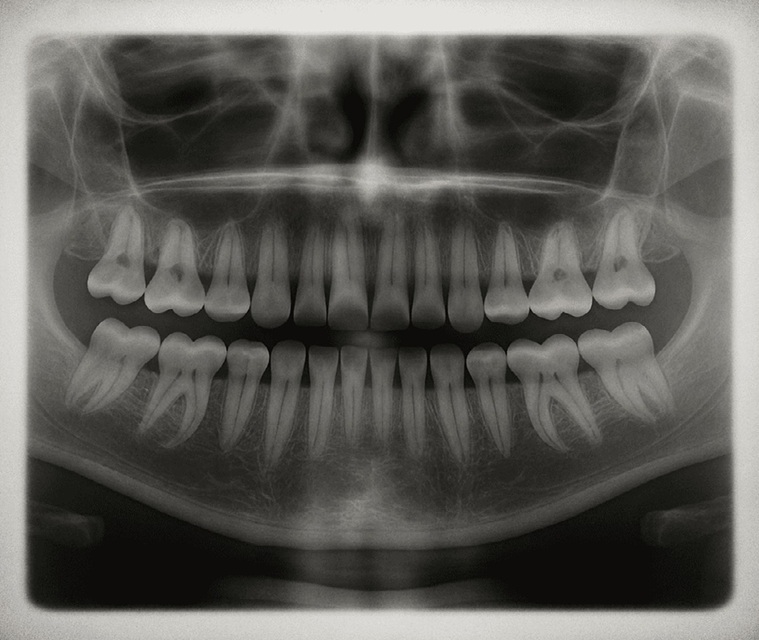

Her insanın ağız yapısında, aslında üçüncü bir diş setinin temelleri (uyuyan diş tomurcukları) halihazırda bulunuyor. Ancak vücudumuzdaki USAG-1 adlı özel bir protein, bu tomurcukların büyümesini baskılıyor. Dr. Takahashi’nin geliştirdiği ilaç, tam da bu proteini hedef alıyor. Protein engellendiğinde, "uyuyan" dişler uyanıyor ve tıpkı çocukluktaki gibi doğal bir şekilde diş etinden yükselmeye başlıyor.

Eylül 2024: En az bir dişi eksik olan 30-64 yaş arası yetişkin erkekler üzerinde insanlı deneyler başladı.

Sıradaki Adım: Yetişkinlerde sorun yaşanmaması durumunda, 2-7 yaş arası diş gelişim sorunu yaşayan çocuklar çalışmaya dahil edilecek.